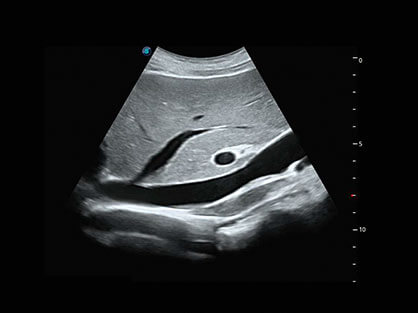

结合百老汇电子游戏官网超宽频带探头技术优势,能够更好地获得高分辨力与高穿透力的平衡,保证图像质量,为临床诊断保驾护航。